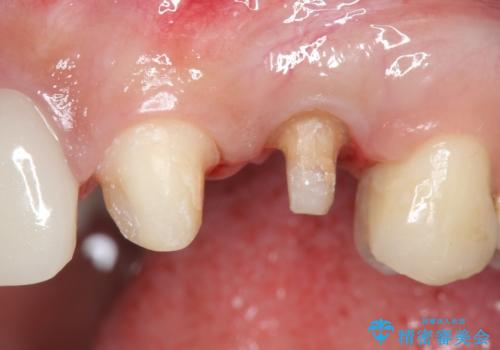

左上4の補綴物を除去したところ縁下歯質だったため、歯牙の挺出を提案し行いました。

挺出終了後は歯肉切除および骨外科により歯周組織を整え、オールセラミッククラウンによる補綴を行いました。

そのため当院では歯周外科手術(歯茎を下げる手術)や歯の挺出による、虫歯が歯茎より深いという問題の解決を推奨しております。